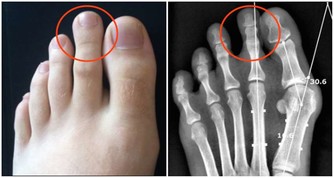

3、神經受累——腰疼並伴隨下肢放射痛

這是腰椎間盤突出症較為常見的疾患之一,主要是因為腰椎間盤各部分(髓核、纖維環及軟骨板),

尤其是髓核,有不同程度的退行性改變後,在外力因素的作用下,椎間盤的纖維環破裂,

髓核組織從破裂之處突出(或脫出)於後方或椎管內,導致相鄰脊神經根遭受刺激或壓迫,

從而產生腰部疼痛,一側下肢或雙下肢麻木、疼痛等一系列臨床症狀。